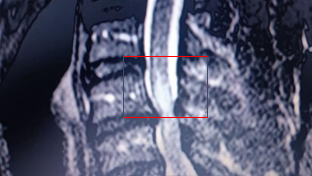

After returning to Uzice (patient’s hometown) from Belgrade, the treatment continues in a quantum medicine private clinic, where the BICOM bioresonance therapy was applied a number of times. After these therapies, the patient underwent rehabilitation treatment. The control MRI of the cervical spine was surprisingly better, as the edema was detected in only one point/area (Figure 3a & 3b), the clinical findings were considerably improved, the hyperesthesia reflexes were not as intense, the spasticity (i.e. the increased muscle tone) was lower than before, and the clonus, which was very pronounced, was hardly noticeable. Due to these results being significantly better than the findings of the first MRI scan, the surgical procedure was decided to be postponed until further notice.

Figure 3a The control MRI of the cervical spine